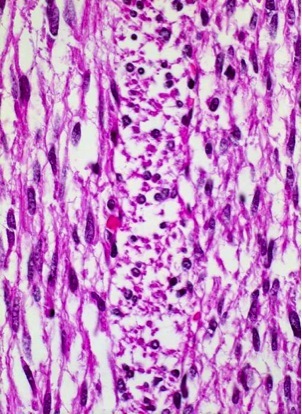

A healthy, 53-year-old man presented with a small, soft, nontender mass of his right upper arm that progressively grew larger and firmer during the 6 weeks before evaluation. Micrograph show below. Dx?

Liposarcoma. Pic shows a lipoblast: very atypical cell with a bizarre nucleus and with vesicles of lipid in the cytoplasm